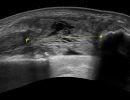

Σύνδεσμοι και Τένοντες Γόνατος

- Ρήξη στον έσω ή έξω Πλάγιο Σύνδεσμο

- Ρήξη ή τενοντοπάθεια τετρακέφαλου τένοντα, επιγοναδιτικού τένοντα ή μηριαίου τένοντα

- Θυλακίτιδα στο χήνειο πόδα

- Σύνδρομο Λαγονοκνημιαίας ταινίας (Runner’s Knee)